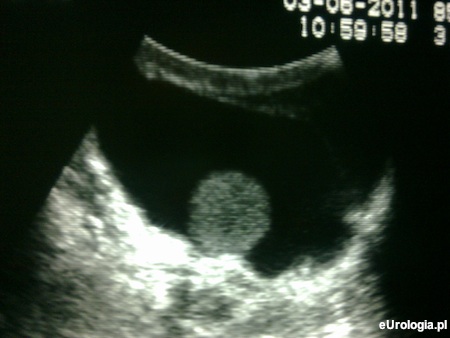

Pozapalny wodniak jądra jest jednym z powikłań zapalenia jądra. Badanie USG moszny jest podstawowym i najważniejszym badaniem wykorzystywanym w diagnostyce obrazowej zawartości worka mosznowego. Nie wiemy jakich rozmiarów jest wodniak w Pana przypadku oraz o jakiej różnicy w grubości płynu Pan pisze. Możliwe jest, że wodniak powiększył się lub lekarze różnie wyliczyli grubość otaczającego płynu (nie ma to żadnego znaczenia w kwalifikacji do dalszego leczenia). Więcej informacji można znaleźć w dziale: leczenie wodniaka jądra.

Fot. Obraz ultrasonograficzny wodniaka jądra.